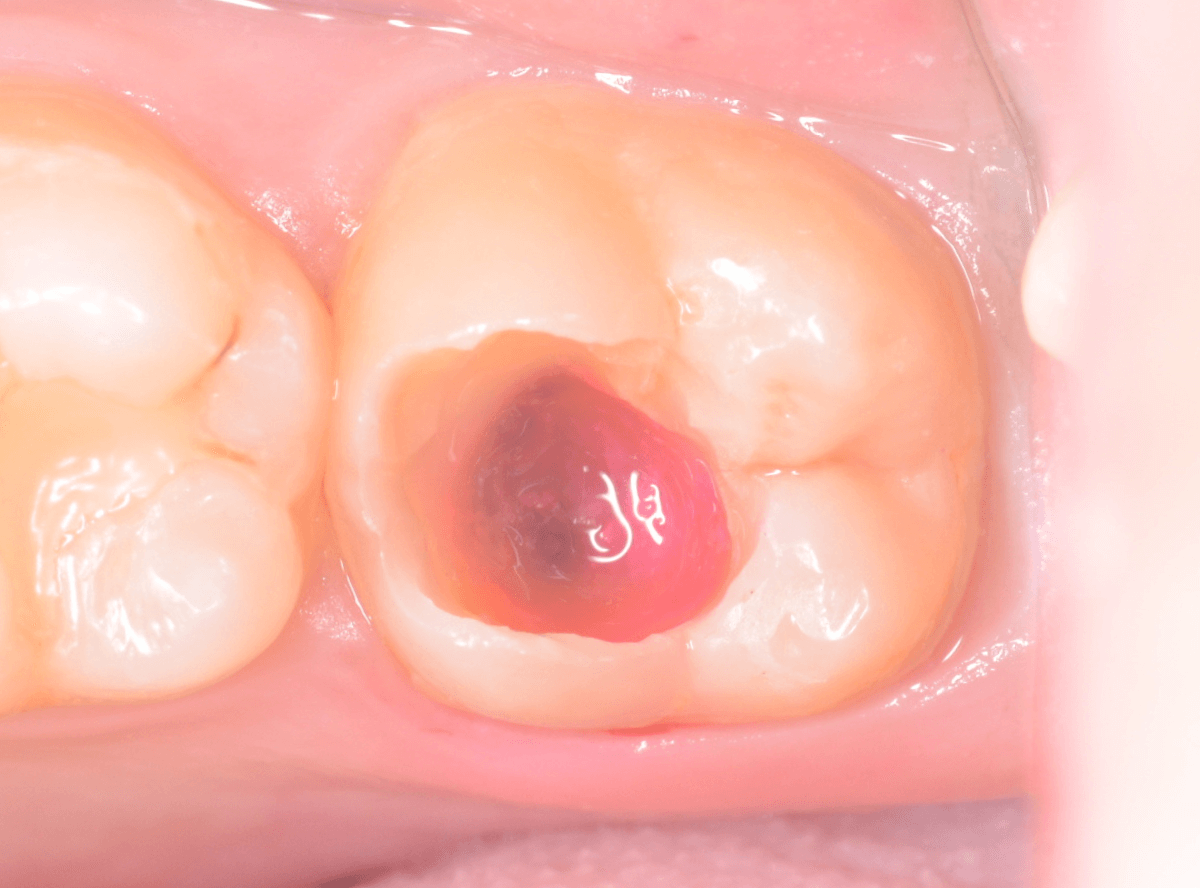

ある程度、虫歯を除去したところで、う蝕検知液で確認します。

赤い部分が虫歯です。

やはり、レントゲン写真で確認した部分が深めの虫歯になっていたようです。

全ての虫歯を除去しました。

お薬をつめて痛みやしみが出ないか、しばらく経過観察しますが、おそらく大丈夫でしょう。

症状が出る前に、検診に来ていただいたことで最小限の治療で済みました。